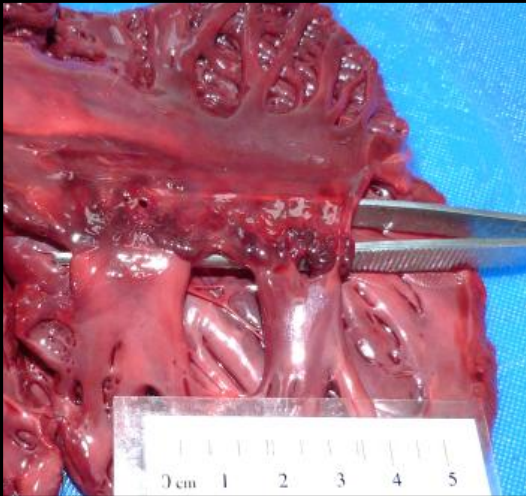

What does this image show?

abnormal kidney with the ureter opened

What areas or the kidney, labelled as 1-5 are abnormal?

1&3

What has occurred in the areas highlighted?

obstruction to blood supply that restricts blood supply to paler areas

What type of change has occurred in the renal parenchyma?

coagulative necrosis